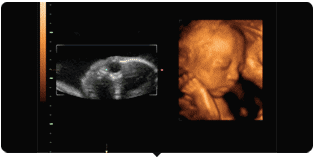

彩超其实还是黑白的,而三维、四维彩超在做出三维、四维图像的时候才是土黄色,也并非彩超就是色彩斑斓的。

被称为彩超,是因为会用彩色标注心脏、血流等指标。彩超的分辨率会比一般黑白B超高一些。而因为能用彩色标注血流,当脐带绕颈的时候就会看见宝宝的脖子上呈U形或者W形的血流,对是否脐带绕颈也就一目了然了。

四维彩超能够多方位、多角度地观察胎宝宝在宫内的实际生长发育情况,为早期诊断胎儿先天性体表畸形和先天性心脏病等提供准确的科学依据。

通过四维彩超可以看到宝宝的表情动作,更为重要的是,它能够多方位、多角度地观察宫内胎儿的生长发育情况,为早期诊断胎儿先天性体表畸形和先天性心脏疾病提供准确的科学依据。

第1大亮点

盐城艾琪儿妇产医院引进的美国GE-E8四维彩超,是目前最先进的彩色超声设备,被誉为“神奇彩超”,能360°立体展现胎儿各器官的发育情况,是应用于胎儿产前排查畸形及缺陷儿的终极诊断,并完整纪录胎儿宫内高清动态的尖端设备,它用出色的人体工程学设计,不存在电离辐射和电磁辐射,对人体组织没有任何影响,而且医学使用的超声属于低强度,低于94毫瓦/立方厘米,对胎儿没有任何危害,所以准妈们可以放心进行孕检,不用再担心是否会有损宝宝的健康